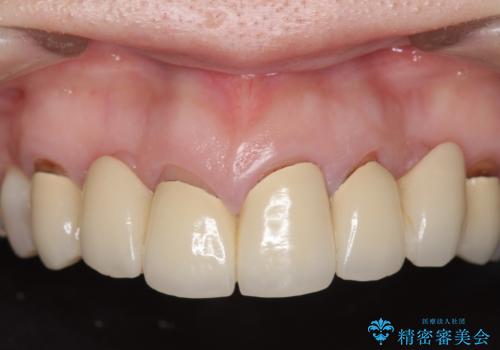

- 昔治療した前歯の被せ物の見た目を改善したいといらっしゃった方の症例です。

左上4番目の歯から右上3番目の歯まで計7歯のクラウンを除去し、オールセラミッククラウンによる補綴を行いました。

今回用いたオールセラミッククラウンはジルコニアフレームという白い素材の上にセラミックを盛っているため、審美性が非常に高いのが特徴です。